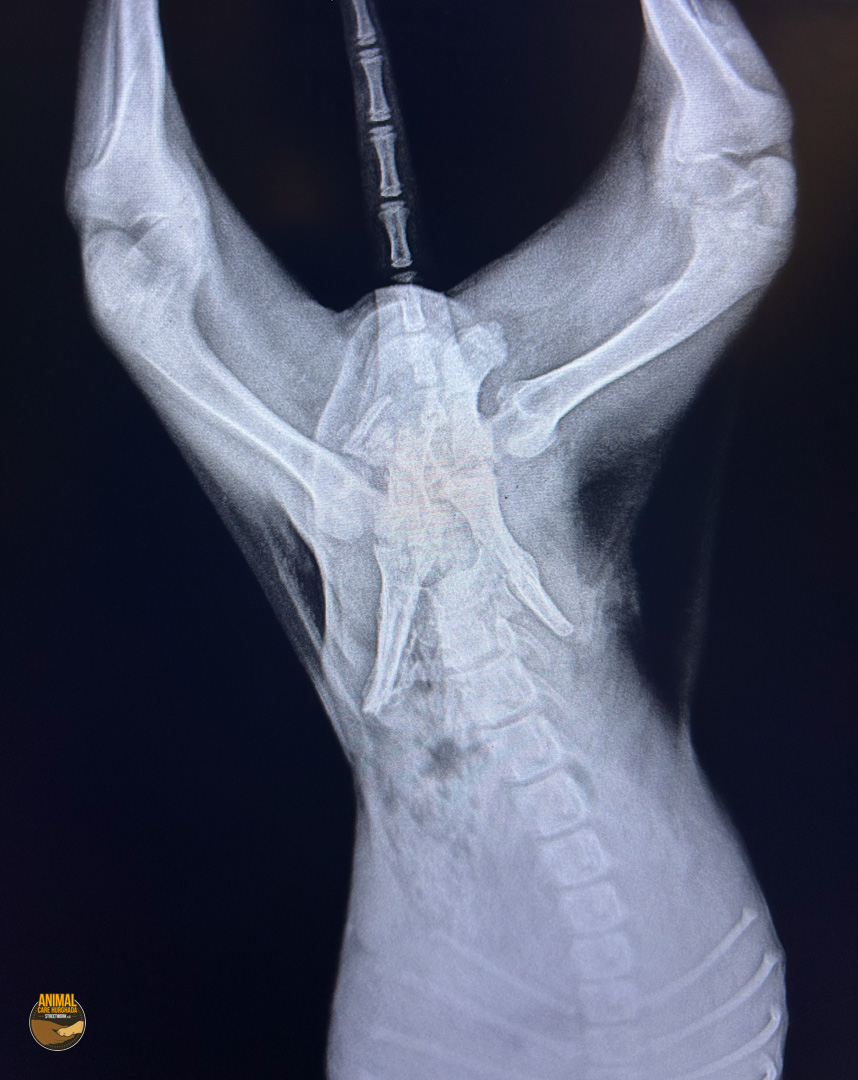

Sammy-Sunshine ist ein junger Hund – noch ein echter Welpe, der voller Energie, Lebensfreude und Neugier steckt. Trotz seines schweren Starts ins Leben hat er seinen fröhlichen Charakter nie verloren. Er kam stark abgemagert und mit einer großen offenen Wunde an der rechten Körperseite zu uns ins Center. Unsere Tierärzte haben ihn sofort erstversorgt, und am nächsten Tag wurde er in der Top Vet´s Clinic geröntgt. Leider ergab das Röntgenbild eine schlimme Diagnose: Sammy hat ein gebrochenes Becken, das nicht operiert werden kann. Eine vollständige Heilung wird es also nicht geben.